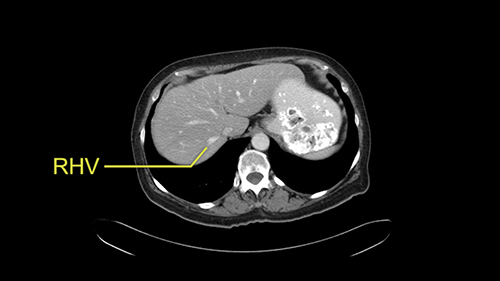

So I would then focus on the hepatic outflow because that’s the way we do the operation is by mobilizing the liver. So the vena cava looks quite normal. The right hepatic vein looks quite normal. There are no large additional outflow veins from the right lobe which would generate slowing down moments. The hepatic artery is unremarkable and is not usually an issue we can define the anatomy quite clearly at surgery.